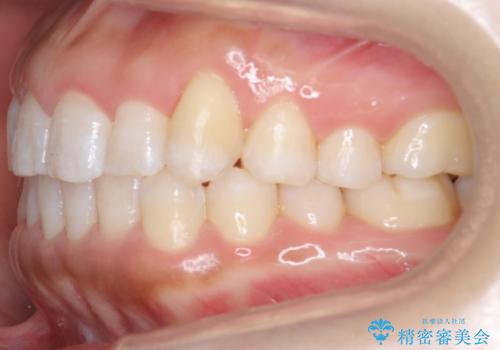

八重歯を非抜歯で マウスピースで治療 奥歯を後ろに下げてすき間を確保

奥歯を後ろに下げてすき間を確保し、八重歯を引っ込めて並べる治療を行いました。

かなり真面目に使っていただいた印象で、綺麗に動きました。